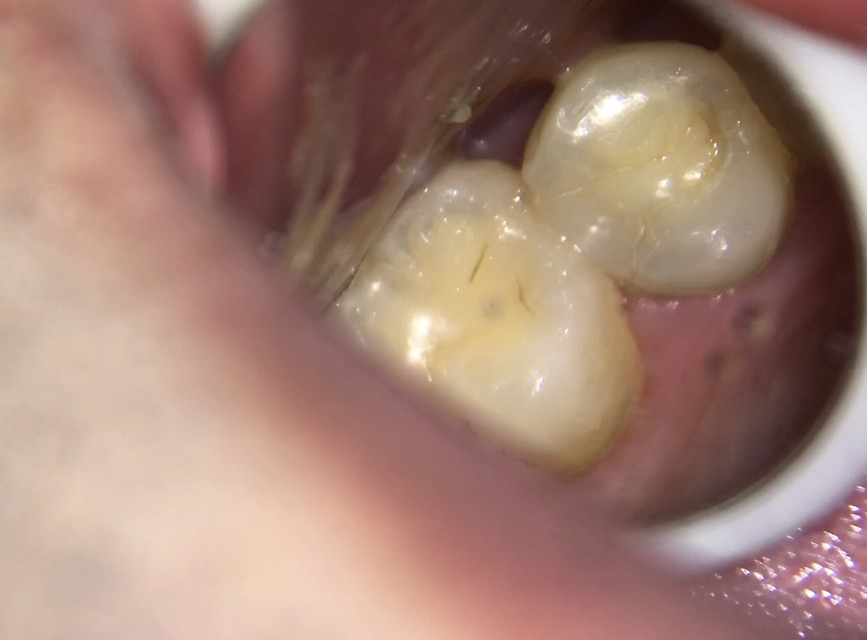

40代男性 上顎第二小臼歯が2次カリエス

口腔内/レントゲン画像